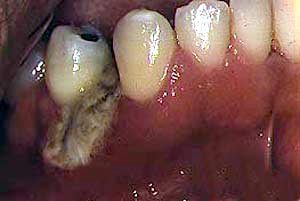

|

Secuestro óseo |

Ocasionalmente otras bacterias pueden presentar ulceración oral

como el mycobacterium avium intracellularae, mycobacterium

tuberculosis, E.coli, actinomyces, Klebsiella y pseudomonas.

Se ha descrito en un número pequeño de casos, Angiomatosis bacilar

oral causado por Rochalimaea henselae. |